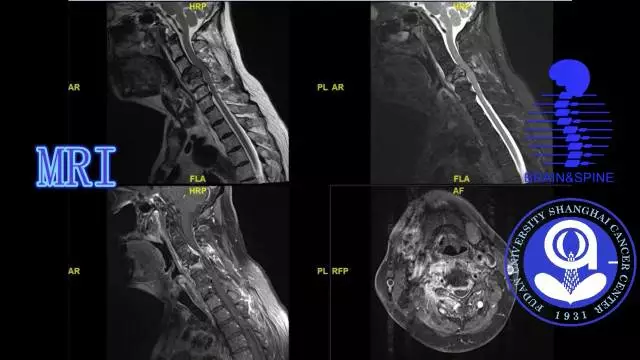

病史简介

手术过程

术后情况